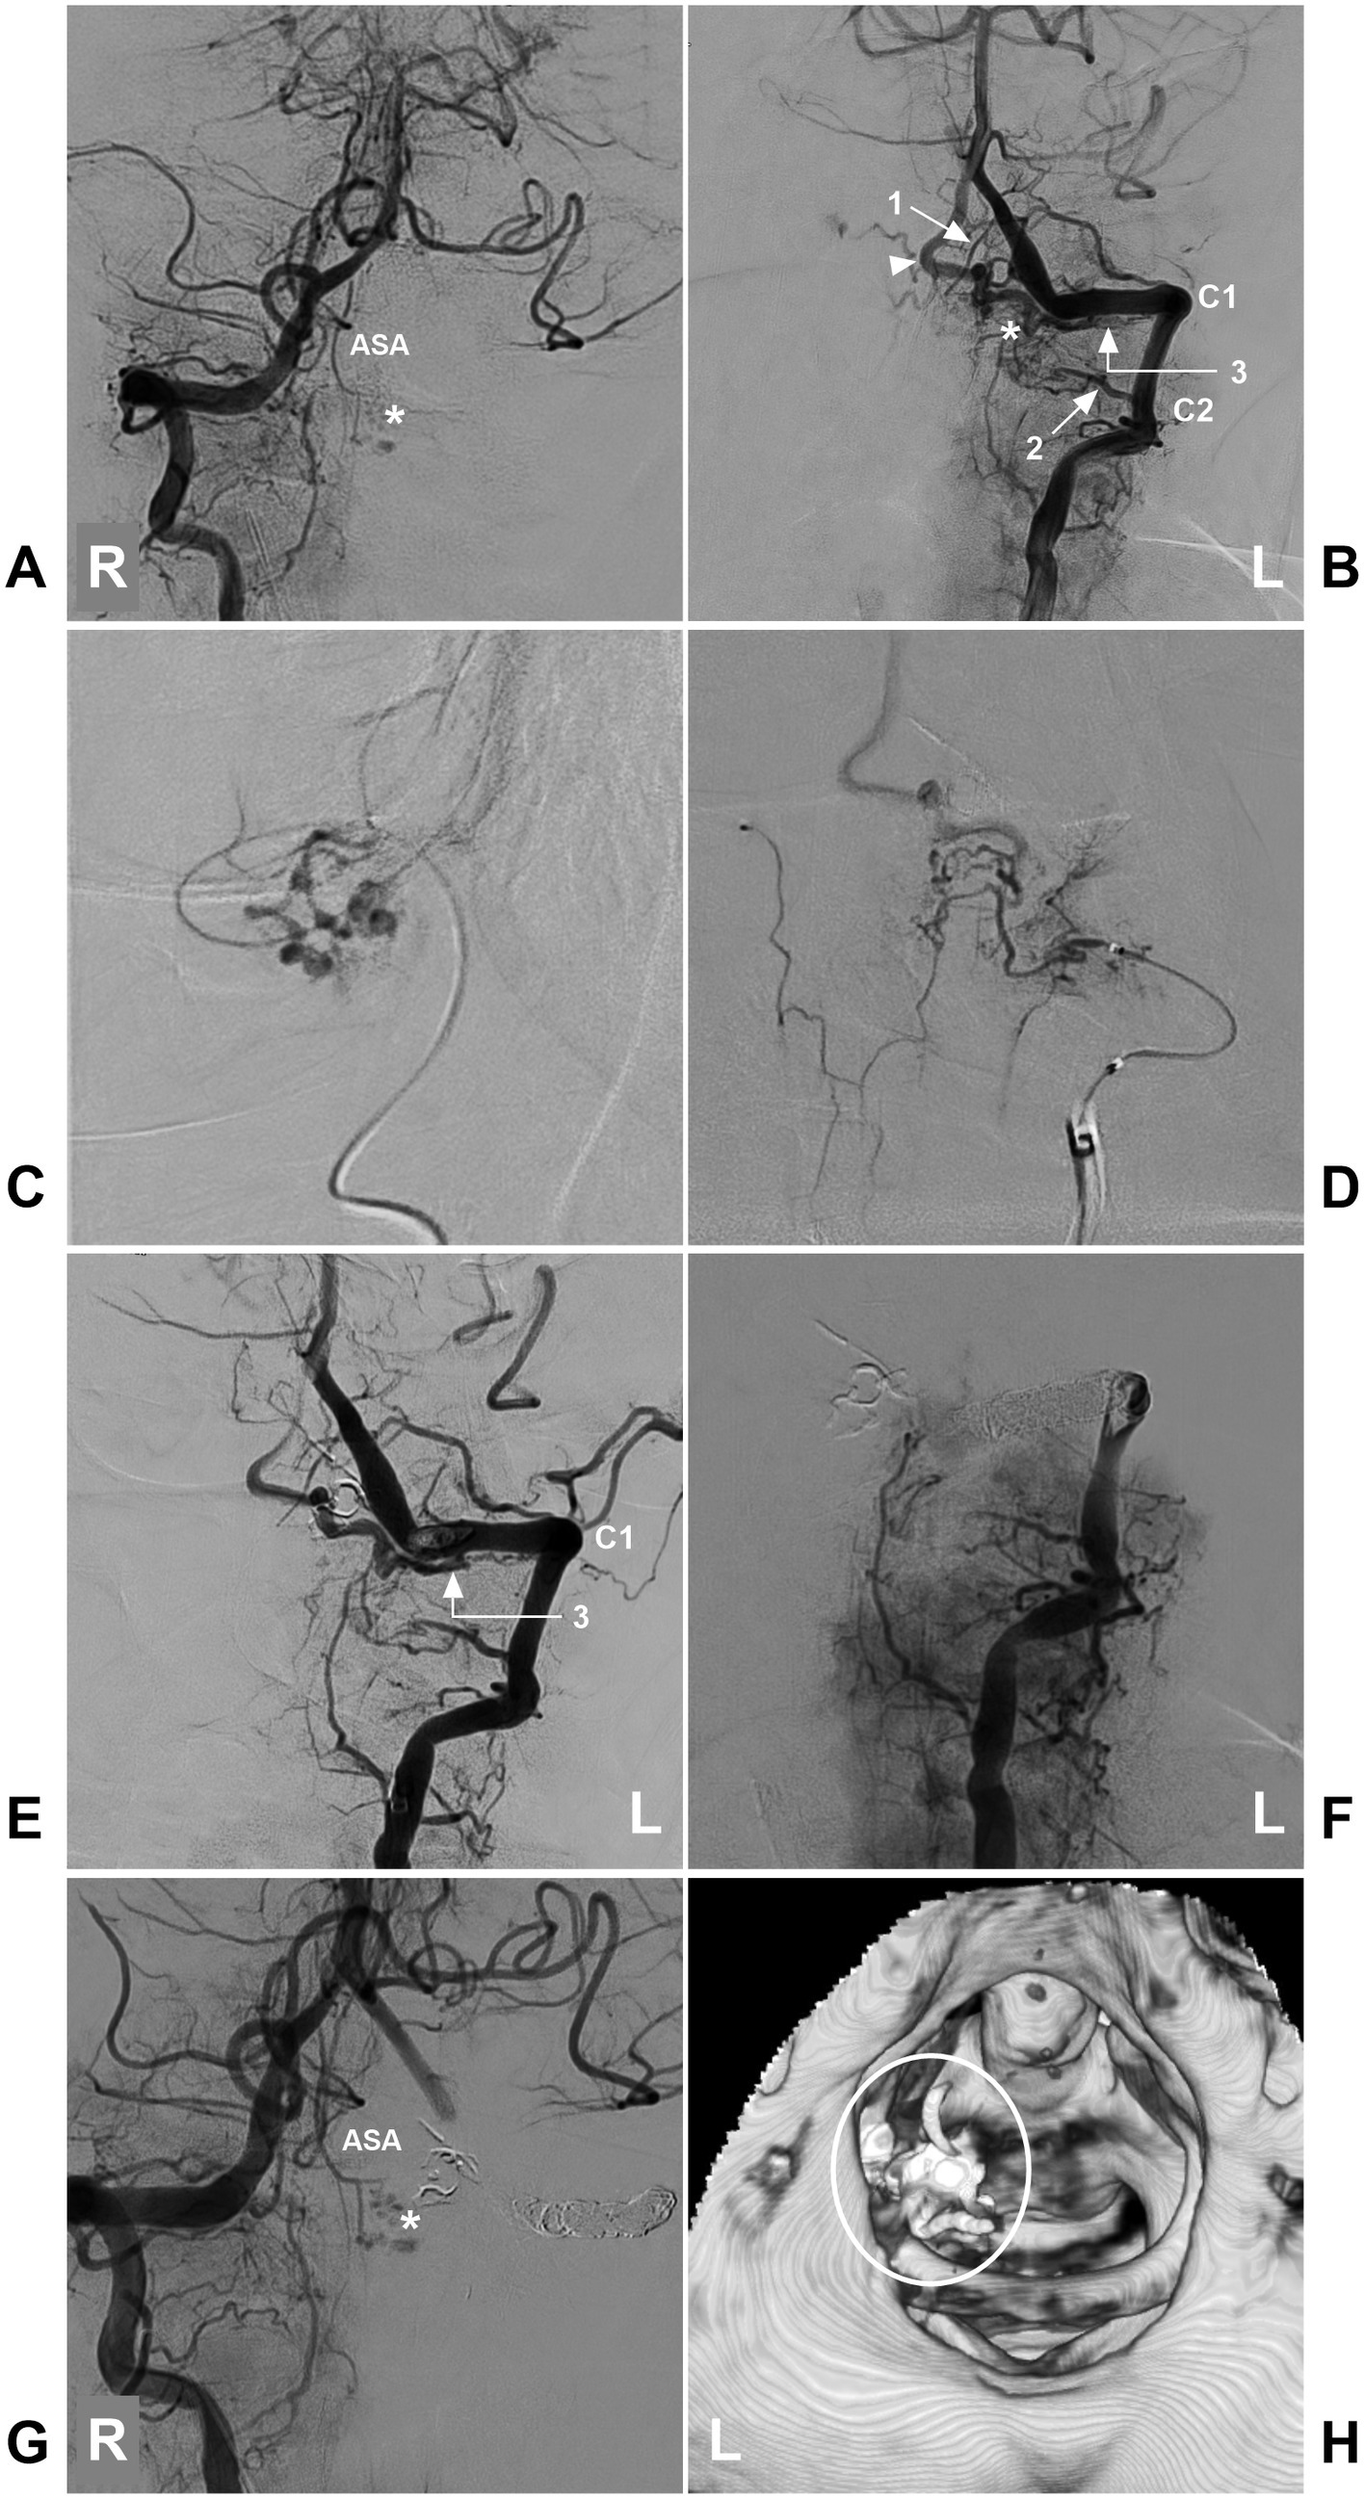

Figure 11

Incomplete EVT in a high cervical CCJ RAVF. (A) DSA of the left VA showing that the ASA supplied the AVF (asterisk). (B) DSA of the right VA showing that the AVF (asterisk) was fed by a brainstem perforating branch of the VA (arrow with number 1), the C2 (arrow with number 2) and C1 (arrow with number 3) radicular arteries, and the arrowhead indicates the draining vein. (C) Selective angiography of the brainstem perforating branch of the VA (arrow with number 1 in B) showing it to supply a part of the AVF. (D) Selective angiography of the C2 radicular artery (arrow with number 2) showing it to supply a part of the AVF. (E) After casting Onyx via two feeding arteries (numbers 1 and 2 in B), DSA of the left VA showing that the AVF was supplied by the C1 radicular artery (number 3 with arrow), confirming RAVF presentation. (F) DSA of the left VA showing that the VA was completely occluded by coiling, and the AVF could not be seen. (G) DSA of the right VA showing a part of the AVF (asterisk) was left. (H) Post-EVT CT reconstruction showing casting Onyx (ellipse), indicating the location of the RAVF. ASA, anterior spinal artery; AVF, arteriovenous fistula; C1-2, first and second cervical vertebrae; CCJ, craniocervical junction; CT, computed tomography; DSA, digital subtracted angiography; EVT, endovascular treatment; L, left; R, right; RAVF, radicular AVF; VA, vertebral artery.